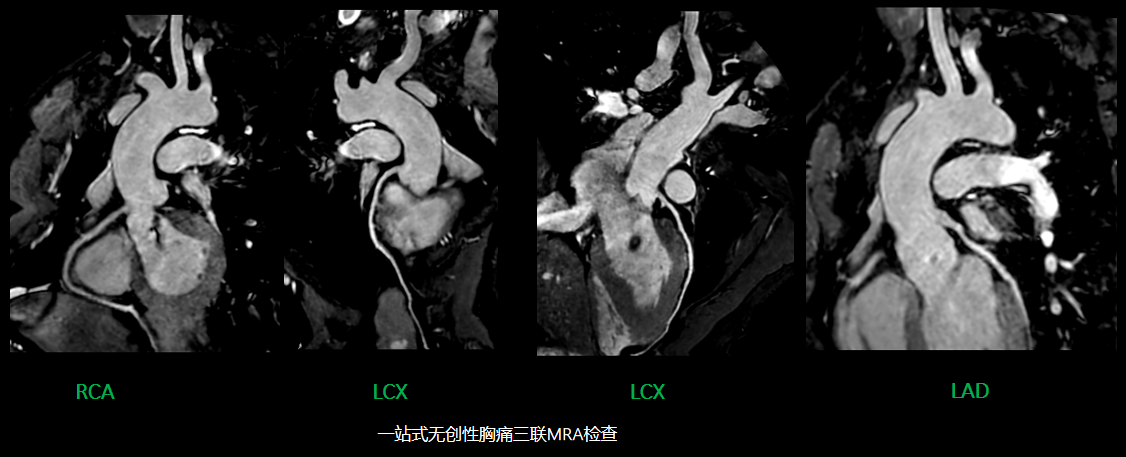

7.心脏磁共振可以做不用药的冠脉成像,心脏造影及功能成像采用压缩感知技术,成像速度和成像质量都有很大提升,对临床诊疗具有重大帮助。